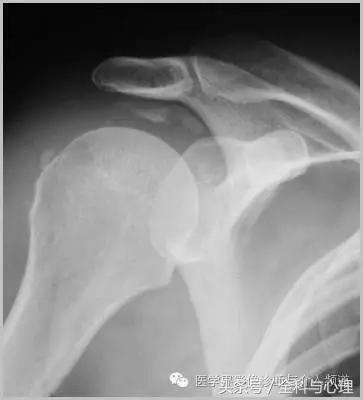

一、肿瘤样钙质沉着症

累及多个关节,范围较大,表现为多房囊状的高密度影。

肿瘤样钙质沉着症